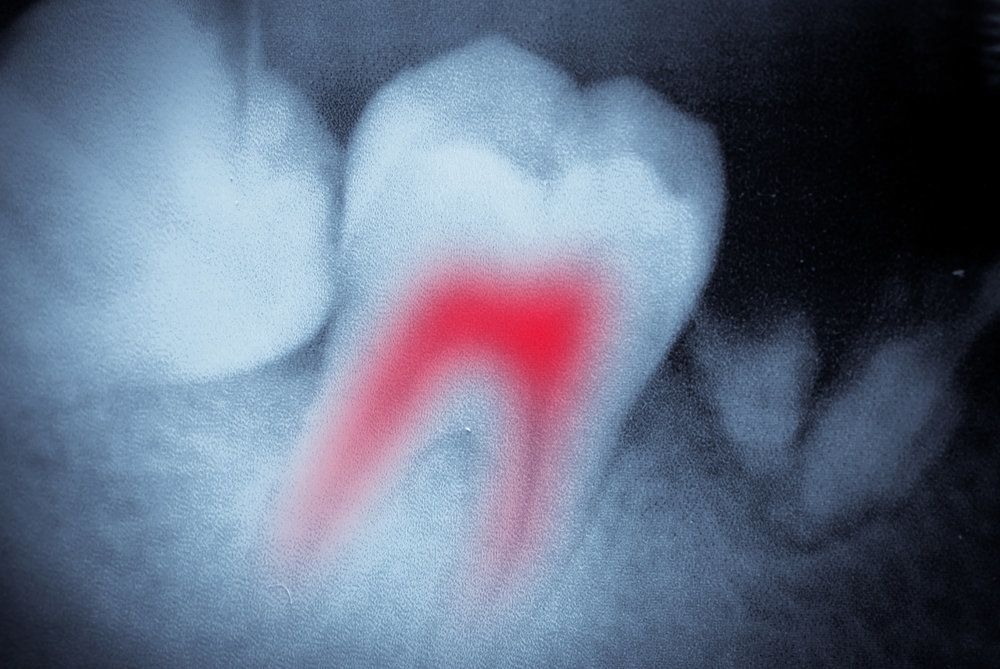

Root Canal Treatment

Root canal treatment is a much-feared dental procedure, but it need not be. Dr. Siegel has the experience to perform root canal treatment with minimal discomfort. In fact, many of our patients have said that it is similar to replacing amalgam fillings with tooth-colored fillings.